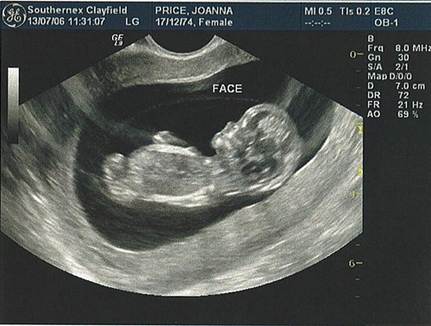

Врачи рассказали об опасности УЗИ во время беременности

Специалисты из Медицинской школы Бостонского университета нашли подтверждение предположениям о том, что УЗИ может привести к развитию аутизма у плода.

Проанализировав данные о количестве сеансов УЗИ и их мощности, ученые пришли к выводу, что развитие детского аутизма в этих случаях было связано с более глубоким воздействием ультразвука на разных этапах беременности.

При этом исследование показало, что дети с аутизмом в среднем подвергались даже меньшему воздействию УЗИ, чем остальные участники. Врачи подчеркивают, что обнаружена связь исключительно между глубиной проникновения ультразвука и данным заболеванием. Указаний на связь аутизма с количеством и длительностью сеансов не обнаружено.